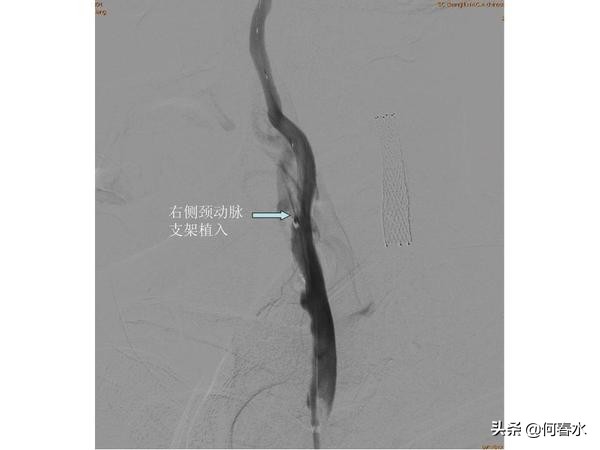

患者至今随访5年,支架通畅,头晕等脑缺血症状完全消失。但是春节后再次出现头晕不适,在职工医院检查发现右侧颈动脉重度狭窄,右侧颅内梗塞病灶,左侧颅内未有梗塞病灶。入住我科后,造影检查发现:右侧颈动脉重度狭窄伴有溃疡形成,左侧颈动脉支架通畅,右侧肾动脉重度狭窄。

右侧颈动脉重度狭窄且伴有溃疡,若采用保护伞类远端保护装置极有可能在通过保护伞的时候将狭窄处的血栓或斑块碰落引起脑梗塞,所以我们采用最先进的近端保护装置—MOMA阻断球囊技术,有效提高了手术的安全性。

(2)颈动脉支架预防脑梗塞的有效性:患者5年前左侧颈动脉重度狭窄,左侧颅内梗塞病灶,5年来植入颈动脉支架通畅良好,现在CT复查未见左侧颅内梗塞病灶,有力地证明了颈动脉支架预防脑梗塞的重要作用;